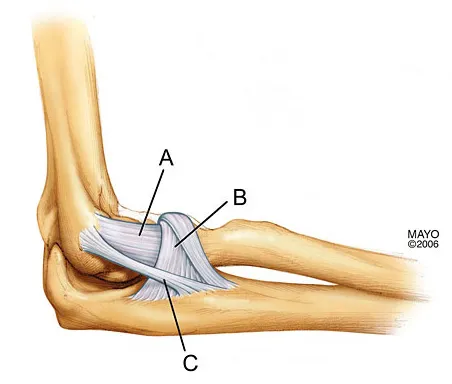

Which of the following ligaments is most commonly involved in posterolateral rotatory instability of the elbow?

Explanation